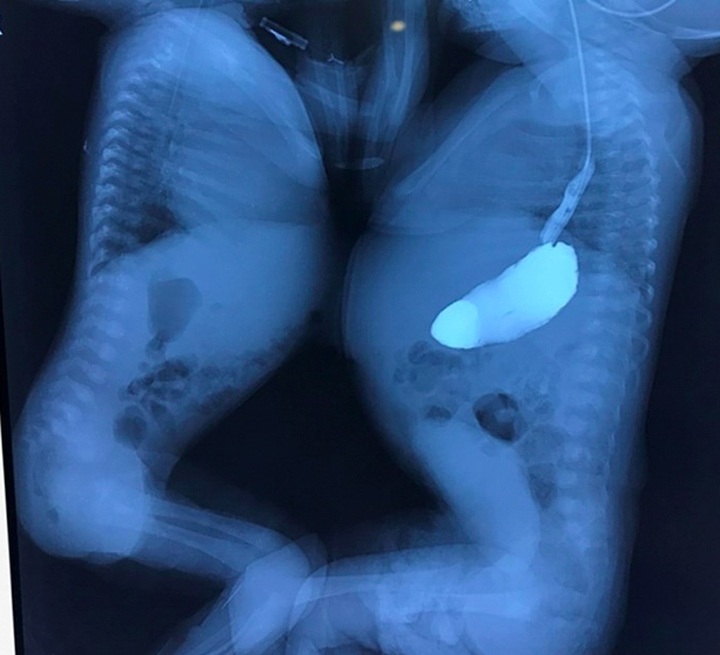

The two infants, V.N and V.T, were found to be conjoined twins when the mother was pregnant at 33 weeks. Local doctors performed a caesarean section seven weeks later, and the two babies were born weighing 2.2kg and 2.8kg respectively.

Meanwhile, V.N had respiratory failure and pustules all over the body. Through echocardiography, doctors of the Lao Cai provincial General Hospital found V.N also suffered atrioventricular septal defect.

After careful examinations, the Hanoi-based doctors concluded that V.T is in stable health while V.N is in critical condition.

V.N suffered atrioventricular septal and single ventricle defects, severe atrioventricular valve regurgitation, aortic disruption, arterial inversion, and pulmonary atrophy.